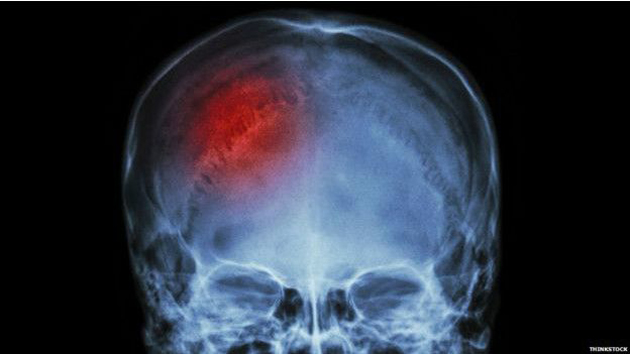

Foto: El sistema de salud pública británico, el NHS, estima que una de cada cuatro personas que sufren un derrame cerebral mueren.

El NHS estima que una de cada cuatro personas que lo sufren mueren, y los que sobreviven con frecuencia padecen problemas serios a largo plazo a consecuencia del daño en el cerebro.